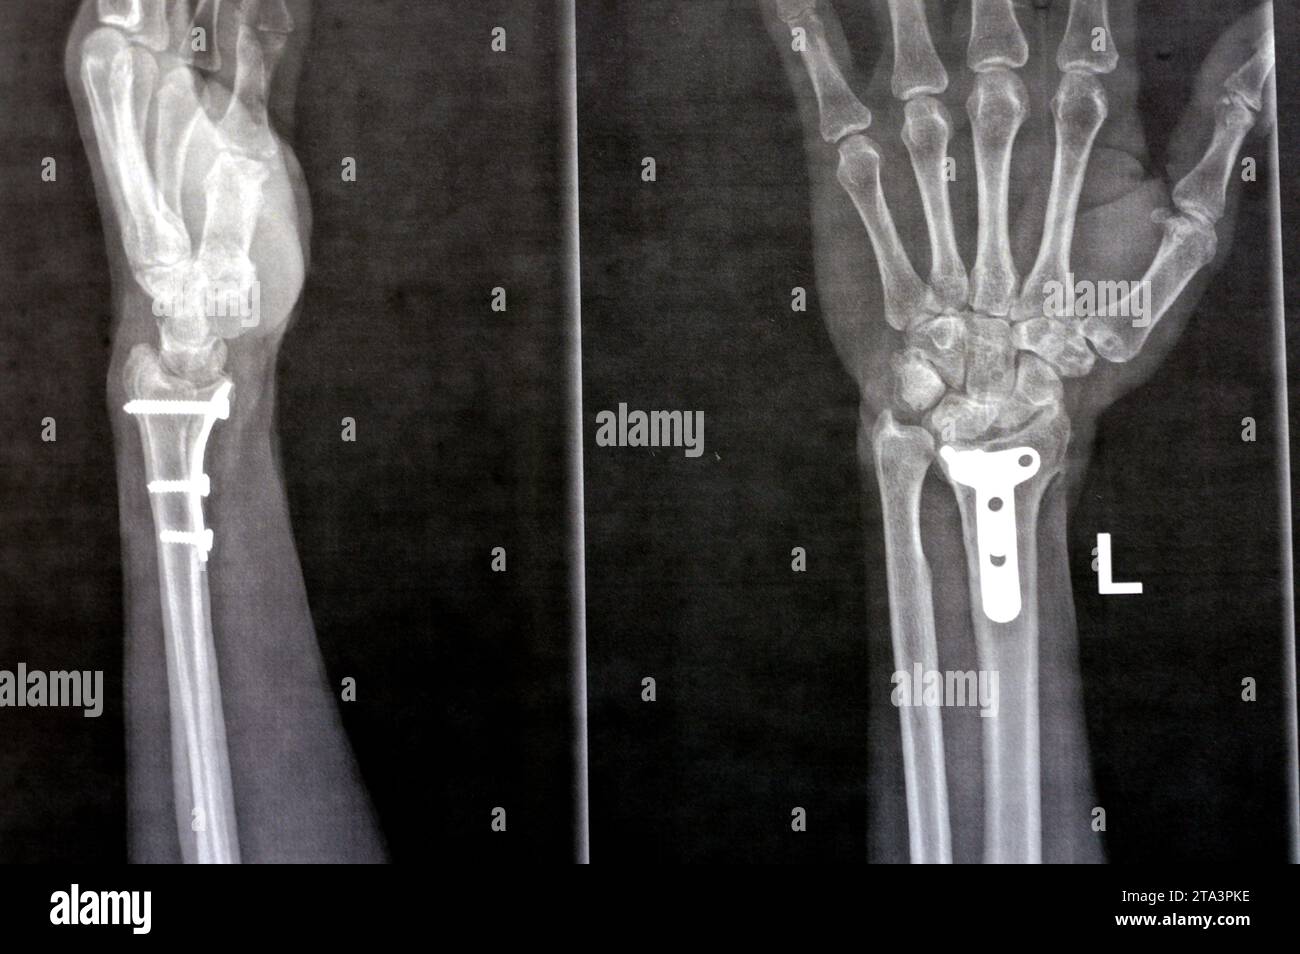

Fissure Fracture X Ray . 'toddler's fracture' = tibial spiral fracture in a toddler. It is necessary when studying the x. Stress fractures of the tibia result from repeated low force trauma. When a person has a bone fracture, one of the first things a person will want to know is how bad it is. Proper description of fractures with knowledge of injury mechanisms, consequent care and complications. It provides an exit route for the chorda tympani from the middle ear to. Transverse, oblique and spiral fractures. The petrotympanic fissure (glaserian fissure) can be visualized on axial and sagittal images (figs. A fissure fracture is noted at the middle third of the right metatarsal bone, more clear on the oblique view (yellow arrow). To determine the severity and treatment/recovery time, doctors will typically perform an. Tibial fractures usually result from high force trauma. Importance of standard radiography of the wrist.

Ulna Fracture X Ray Fissure Fracture X Ray A fissure fracture is noted at the middle third of the right metatarsal bone, more clear on the oblique view (yellow arrow). To determine the severity and treatment/recovery time, doctors will typically perform an. Importance of standard radiography of the wrist. When a person has a bone fracture, one of the first things a person will want to know is. Fissure Fracture X Ray.

Xray Hand. Fracture Image & Photo (Free Trial) Bigstock Fissure Fracture X Ray Importance of standard radiography of the wrist. 'toddler's fracture' = tibial spiral fracture in a toddler. It provides an exit route for the chorda tympani from the middle ear to. To determine the severity and treatment/recovery time, doctors will typically perform an. When a person has a bone fracture, one of the first things a person will want to know. Fissure Fracture X Ray.